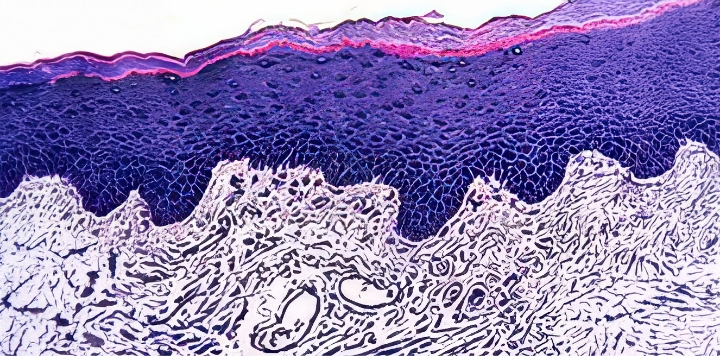

질 조직 정상 수준으로

회복되며 질 건조증 개선

JS트로겐 투여 시, 각화세포층을 포함한

질 조직이 정상에 가깝게 회복